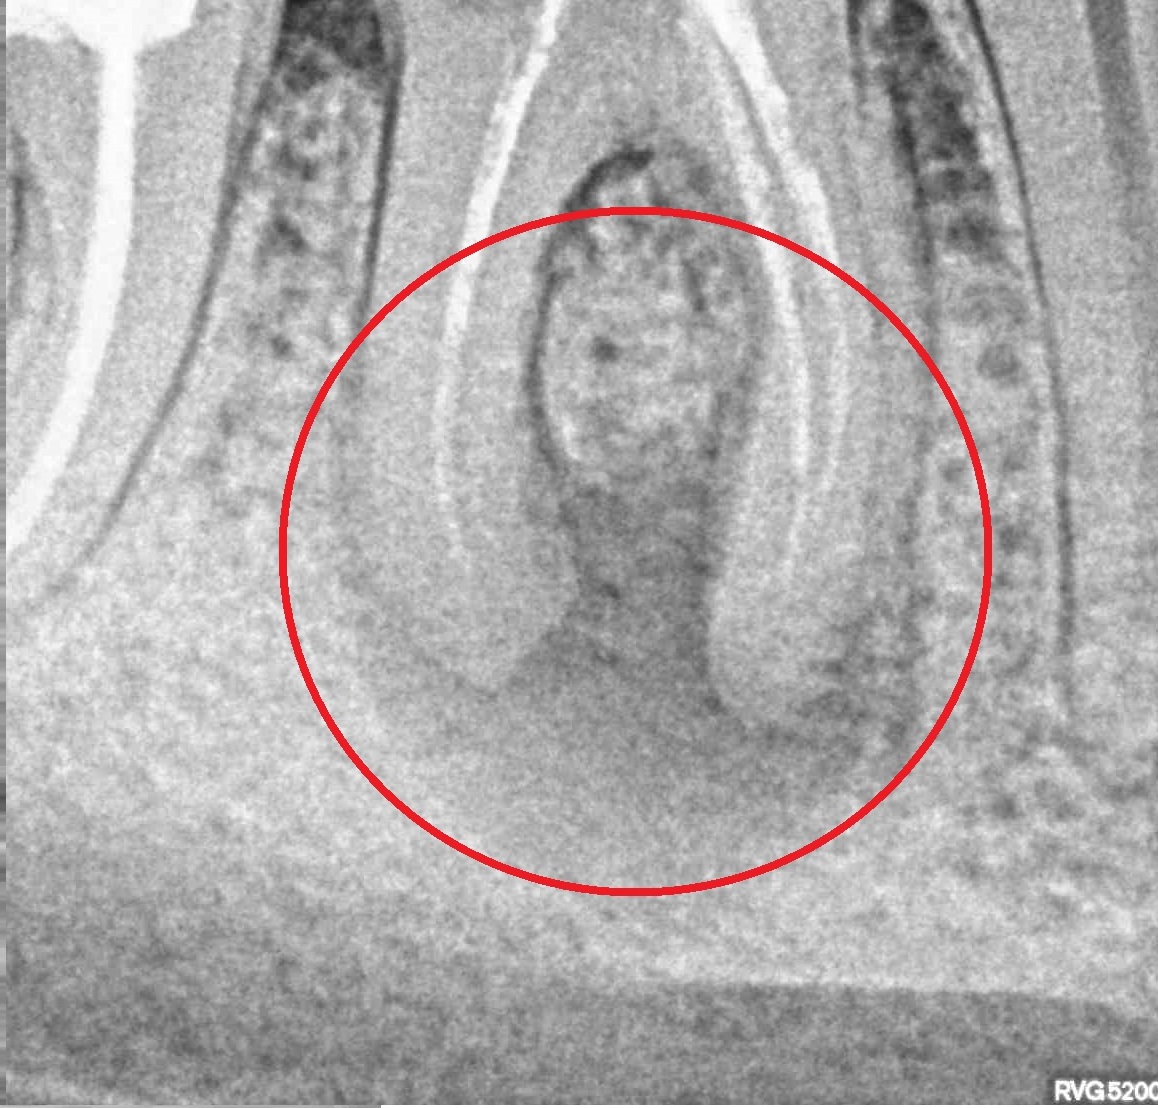

- Лечение периодонтита

Проблема

Пациент обратился в клинику с постоянными ноющими самопроизвольными болями в зубе, усиливающиеся при накусывании, отечность тканей в области причинного зуба. После детального обследования были обнаружены значительные очаги воспаления на корнях зуба.Решение

Пациенту было проведено эндодонтическое лечение данного зуба. В результате лечения наблюдаем восстановление костной ткани, окружающей зуб.